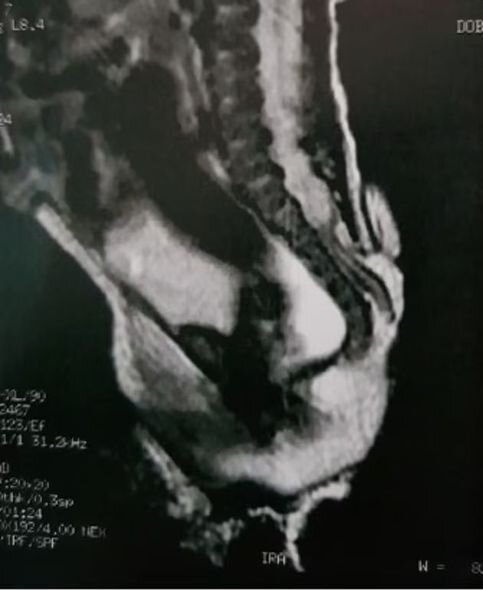

Braziliyada körpə qız altı santimetr uzunluğunda quyruqla doğulub. Quyruq dəri ilə örtülüb.

Həkimlərin fikrincə, quyruq onurğa sütununun əlavəsidir. O, onurğa sütununu çanaq sümüyü ilə birləşdirən lumbosakral nahiyədən çıxır.

Mütəxəssislər əsas onurğa iliyində qüsurların olmasından şübhələnirlər.

Artıq qızın əməliyyat olunduğu bildirilir. Quyruq uğurla çıxarılıb.

Qeyd olunur ki, hazırda uşağın sağlamlığı üçün heç bir təhlükə yoxdur./Oxu.az